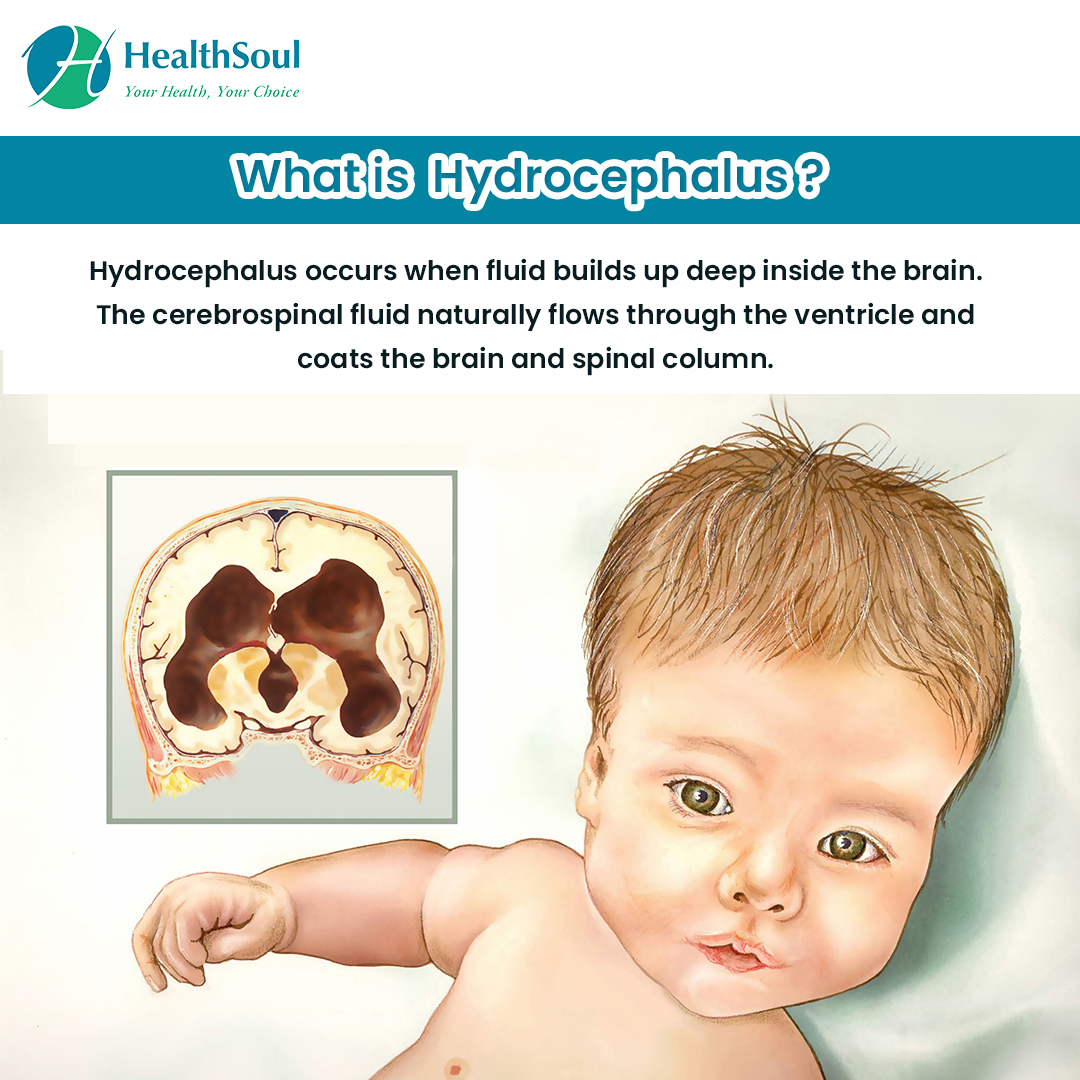

Symptoms And Causes Of Hydrocephalus

Hydrocephalus : Symptoms, Picture, Causes, and Treatment

Hydrocephalus In Infants – Causes, Symptoms & Treatment | Neonatal …